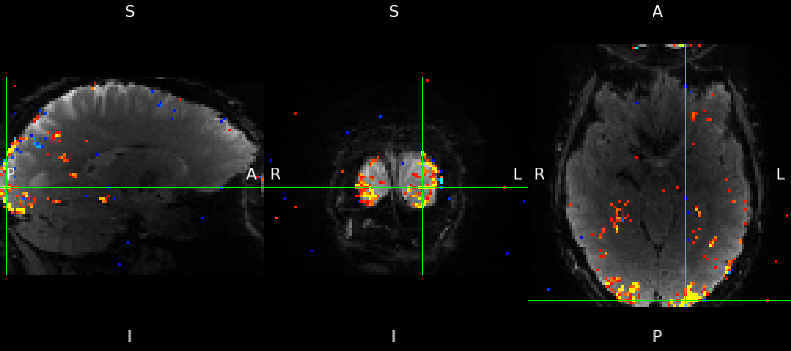

The Post-stats page contains the good stuff - the results of the statistical analysis. Each image displays the fMRI data in the background in grey, and t-statistics in red-yellow, for the statistically significant voxels (voxels where there was no significant activation are not coloured).

If your experiment had two stimuli, and you set up the analysis to Compare condition #1 with condition #2, a total of five tests will have been performed:

- zstat1 - C1 (mean): These results show the activation in response to both of the stimuli combined (e.g. as if they were just a single stimulus).

- zstat2 - C2 (stimulus 1): These results show the activation in response to your first stimulus.

- zstat3 - C3 (stimulus 2): These results show the activation in response to your second stimulus.

- zstat4 - C4 (stimulus 1 > stimulus 2): These results show where the activation in response to your first stimulus was greater than the activation in response to your second stimulus.

- zstat5 - C5 (stimulus 1 < stimulus 2): These results show where the activation in response to your second stimulus was greater than the activation in response to your first stimulus.

There is a collection of time series plots underneath the test results. These plots show the data and the model fit for the most significant voxel, for each of the tests that were performed.

- The red line shows the fMRI data (after preprocessing, e.g. high-pass filtering).

- The blue line shows the best fit of our model to the data.

- The green line shows the “partial” model fit, which can be useful when you have more than one stimulus.